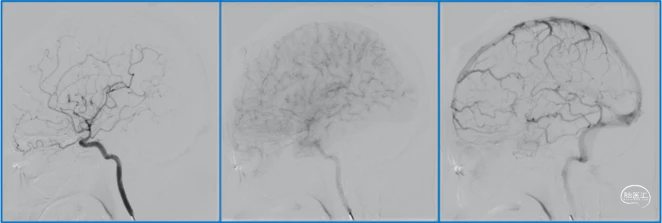

典型病例

![]()

稳妥的外科治疗方案:先介入栓塞颈外动脉的供血动脉,然后显微手术切断颈内动脉的供血动脉,阻断引流静脉,电凝封闭硬膜瘘口。

神经内镜可以辅助确认颞极深部的引流静脉,避免残留引流静脉。